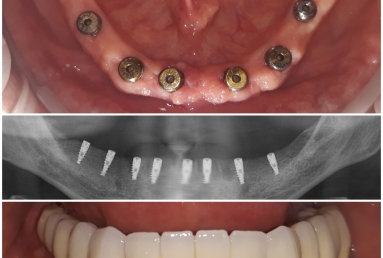

Our patient had advanced periodontal disease with general tooth mobility.

All teeth needed to be extracted and replaced with dental implants. Mobile prothesis were used as temporary restorations.

After implant healing, fixed bridges were made out of porcelain fused to metal.

One more dental implant is needed, but with sinus lift graft, intervention that is postponed for the moment.